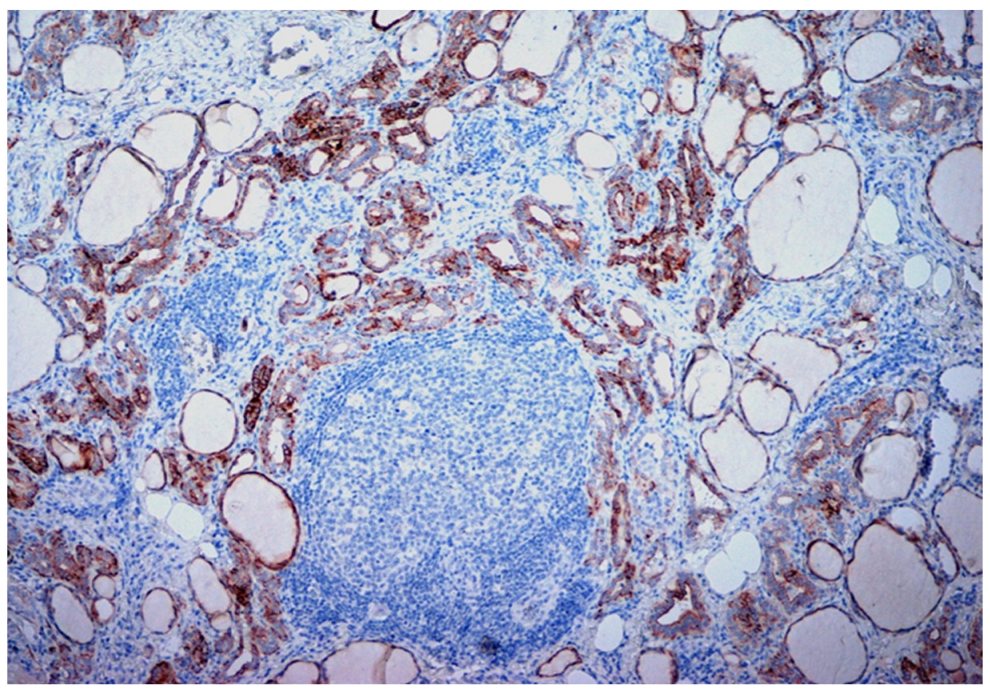

| Thyroid Cancer | +++c/focal n | +c/-n | -c/-n |

| HT | - | +c/-n | -c/-n |

| Adenomas | ++c/focal n | +c/-n | -c/-n |

| Thyroid Cancer | +c/+n | +++c/+n | +c/+++n |

| HT | - | focal c/++n | focal c/+++n |

| Adenomas | ++c/+n | +c/+n | -c/focal n |